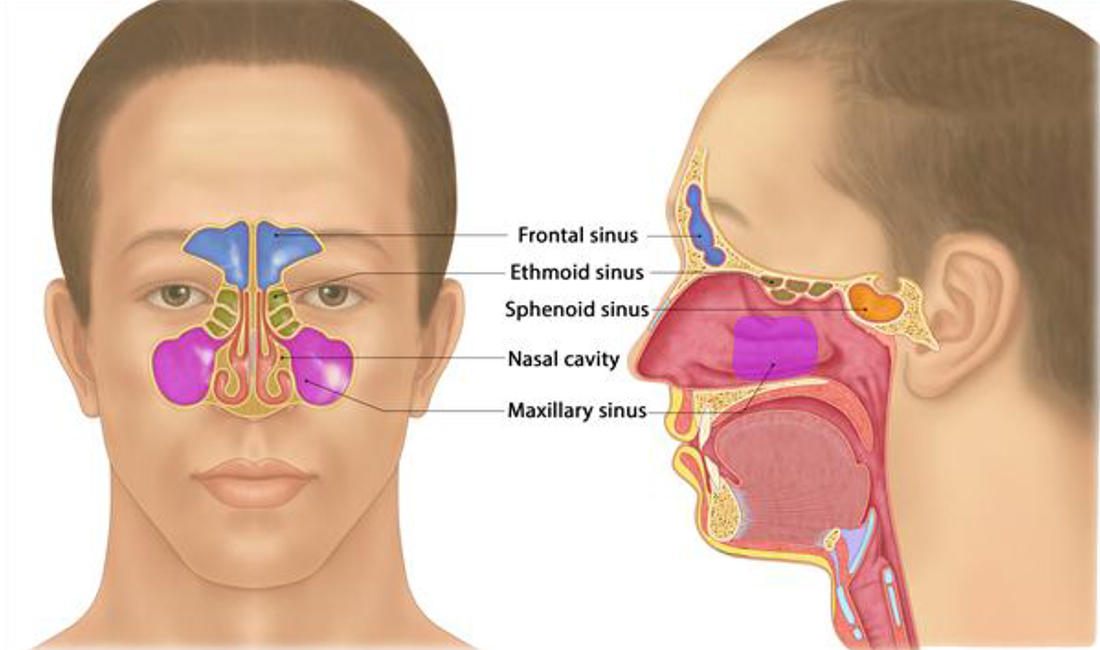

КТ-снимки хронического этмоидита: подробная визуализация